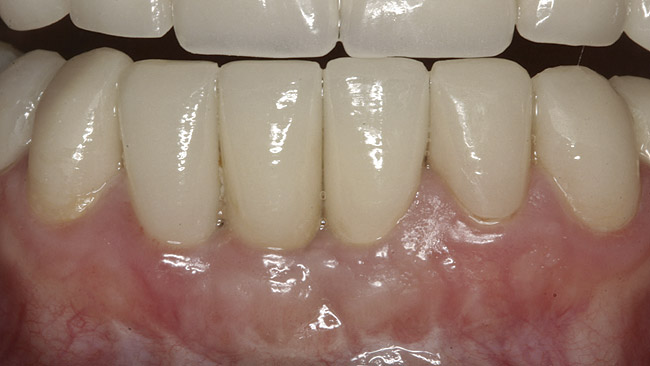

Figure 1  Initial presentation with yellow, poorly color-matched restored mandibular anterior teeth.

Figure 1

A 36-year-old nonsmoking Caucasian woman in good health presented to the author’s periodontal practice to replace tooth No. 26 with an implant. She had presented to her restorative dentist with a chief complaint of yellow, poorly color-matched mandibular anterior teeth (Figure 1). Her medical history was significant for asthma and seasonal allergies for which she took oral montelukast, orally inhaled fluticasone and salmeterol, and oral cetirizine; she also took lorazepam for anxiety. Her dental history was significant for traumatic experiences.